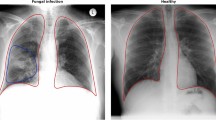

To better understand the factors contributing to low Shapley values, we visualized the most salient local regions in the 65 mislabeled low value chest X-ray images (see Methods). Figure 3a, b show example heatmaps of low value chest X-rays that were mislabeled as pneumonia (Fig. 3a) or no pneumonia (Fig. 3b).

Example heatmaps for (a) low value images that were mislabeled as pneumonia, (b) low value images that were mislabeled as no pneumonia, (c) high value images that were mislabeled as pneumonia. (a) Heatmaps show low activations in relevant areas in the lung but high activations in irrelevant areas outside the lung, suggesting that the input feature vectors favored no pneumonia over pneumonia. (b) Heatmaps show high activations in lung areas indicating pneumonia, suggesting that the input feature vectors favored pneumonia over no pneumonia. (c) Heatmaps show high activations in abnormal lung areas. The first three images show abnormal opacity. The fourth image shows interstitial patterns, predominantly in the upper lung fields. The last image shows abnormal mass in the upper right lung field (i.e. upper left of the image).

In Fig. 3a, the heatmaps had low activations in relevant areas in the lung but high activations in irrelevant areas outside the lung, which suggests that the corresponding feature vectors favored no pneumonia over pneumonia for these images. Unsurprisingly, this pattern existed in the heatmaps of 12 (out of 13) low value images that were mislabeled as pneumonia.

In contrast, the heatmaps in Fig. 3b had high activations in areas that indicate pneumonia, suggesting that their corresponding feature vectors favored pneumonia over no pneumonia. This pattern existed in the heatmaps of 45 (out of 52) low value images that were mislabeled as no pneumonia.

Therefore, the contradictions between feature vectors and labels likely resulted in these 65 mislabeled images being assigned low value.